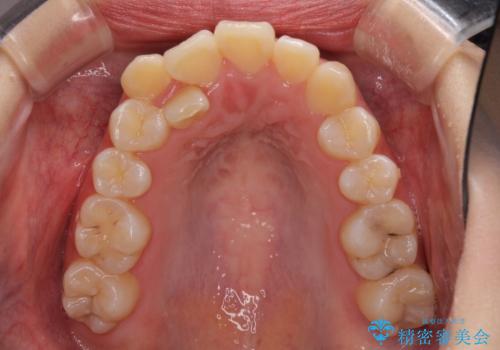

- 八重歯を気にして来院された患者様です。

上下ともに前突感と叢生が認められ、上顎の正中が著しく右側にずれていたため、上下左右第一小臼歯4本を抜歯し、ワイヤー矯正にて治療を行うこととしました。

移動量が多かったため、治療期間は通常より半年~1年ほど長くかかりましたが、上下の正中をほぼ同じ位置にまで移動させることができました。